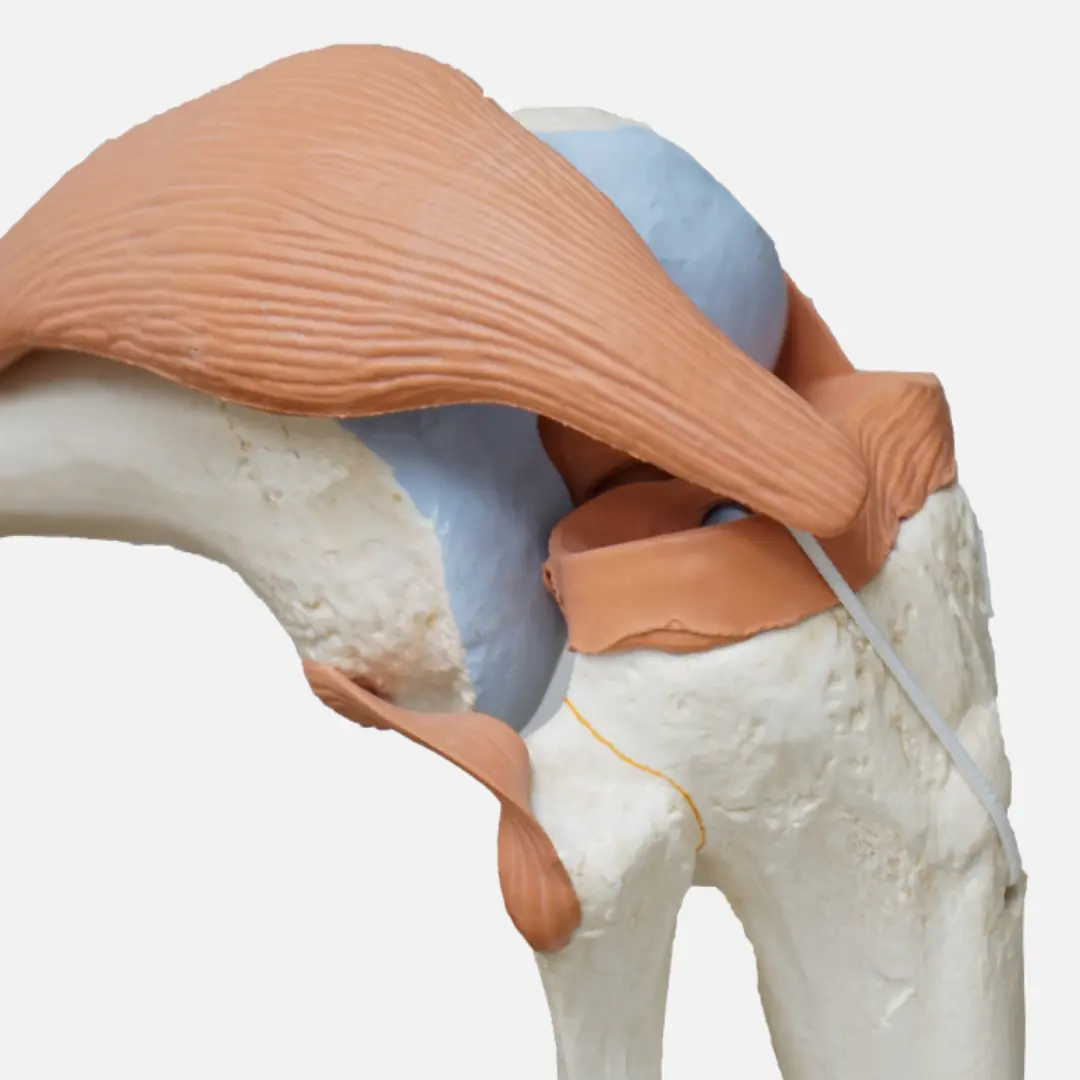

관절염에 좋은 음식 외 관절염에 좋은 것

관절염 관리를 위해서는 음식을 섭취하는 것 외에도 다양한 방법들을 병행하는 것이 중요해요. 함께 실천하면 더욱 효과적으로 관절 통증을 완화하고 기능을 개선할 수 있답니다.

- 적절한 운동: 관절 주변 근육을 강화하는 운동은 관절을 지지하고 안정화시켜 통증을 줄이는 데 도움이 돼요. 수영, 걷기, 요가 등이 관절에 부담을 덜 주면서 근력을 강화하는 좋은 운동입니다.